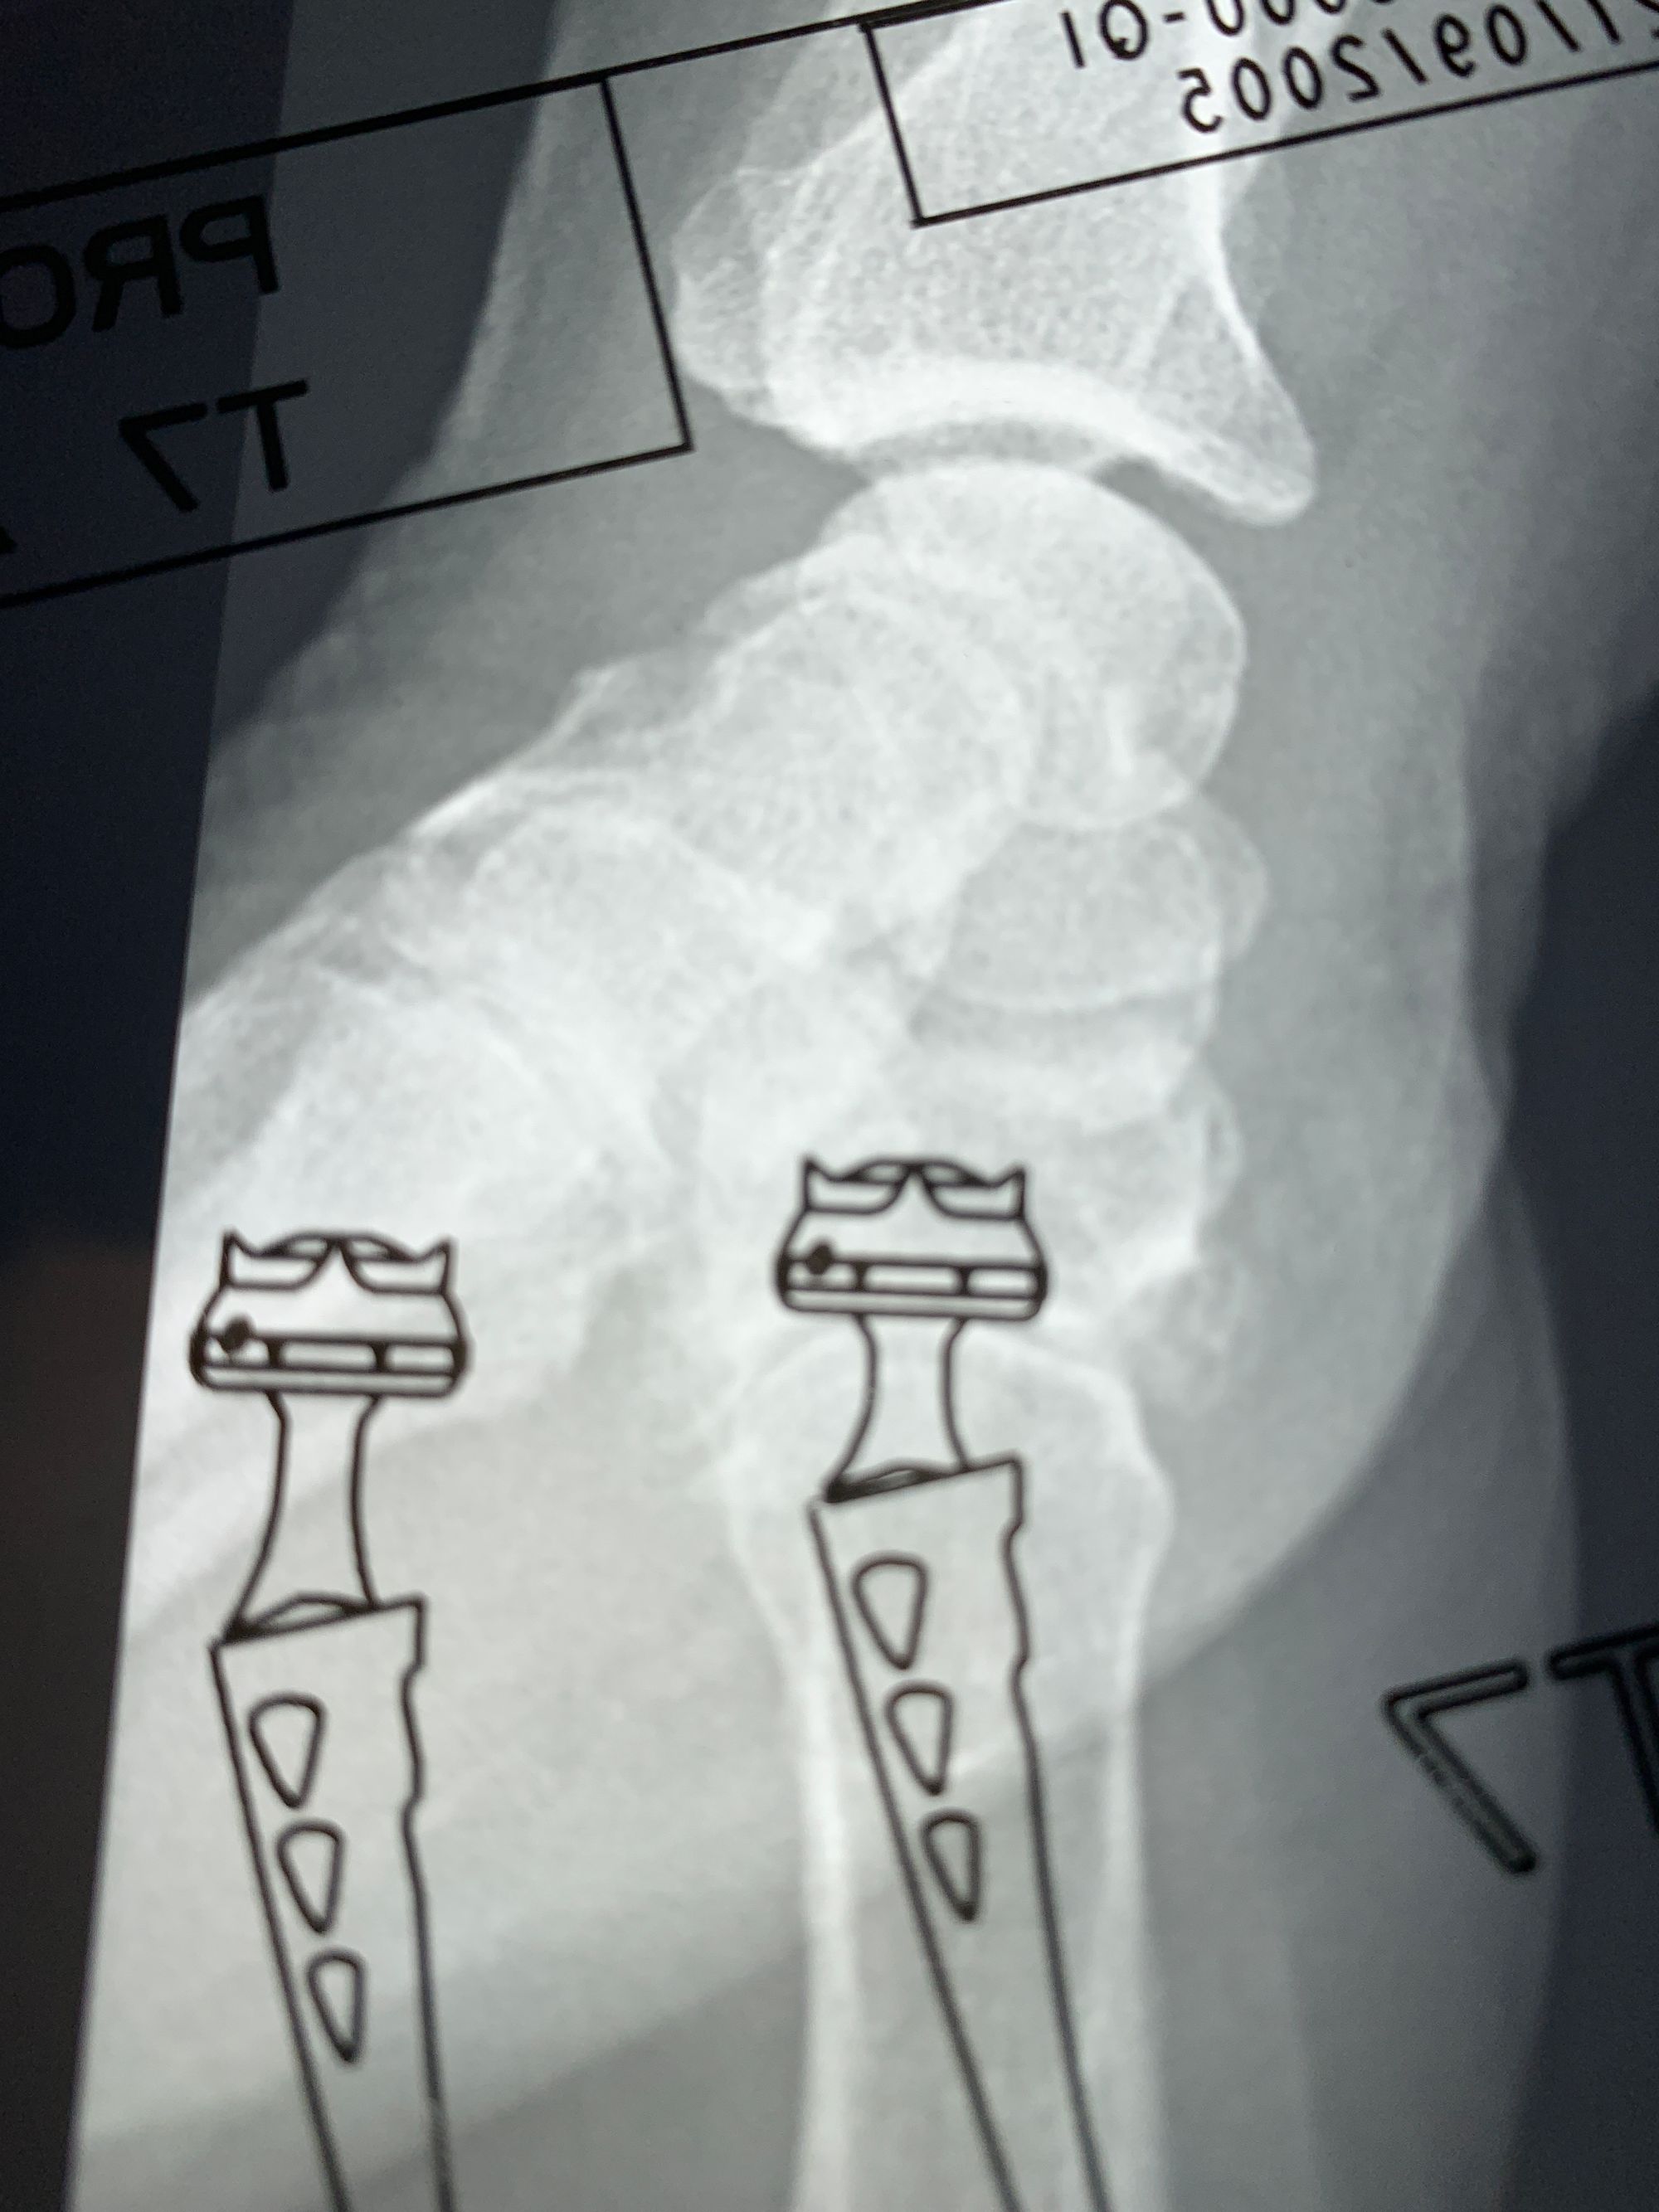

There are also implants that combine both STT arthrodesis and CMC arthroplasty. I have no experience with these devices. Figure 17. Finally, for this same indication of PT arthritis, some surgeons offer a double arthroplasty (STT and CMC) either using a CMC implant and STT spacer or a double spacer.